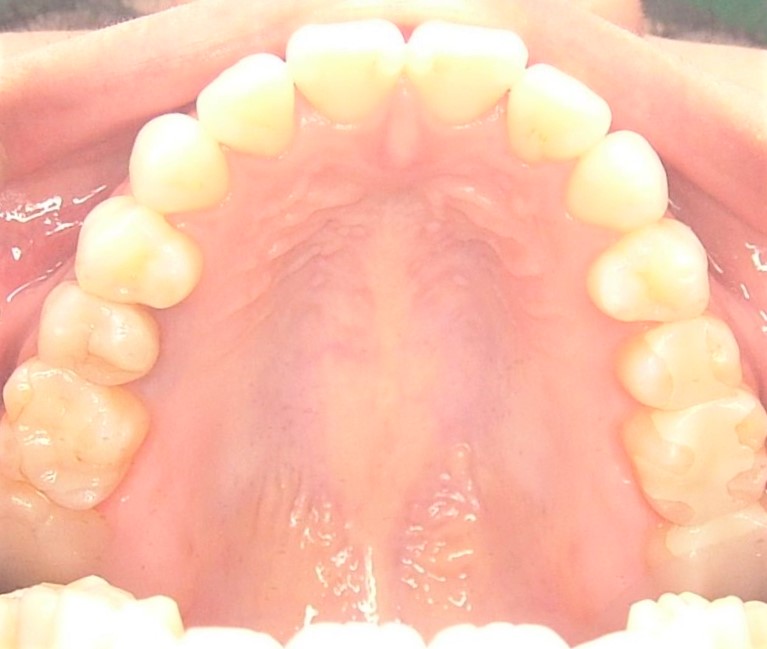

口腔内写真 |

|

| 治療内容 | 掌蹠膿疱症、不定愁訴も治したい。花粉症もあり。ガルバニー電流測定、オリゴスキャン検査、ビタミンDの血中濃度測定 |

|---|---|

| 治療期間・回数 | 5か月・30回 |

| 治療時の費用 | 1,200,000円(メタルフリー代、サプリメント代) ※本症例当時の価格です。最新の費用はこちら |

| リスク・副作用 | 金属除去後に熱が出たそうですが、一時的な好転反応と思われます。このような症状は個人差があるので、特に心配はありません。 |